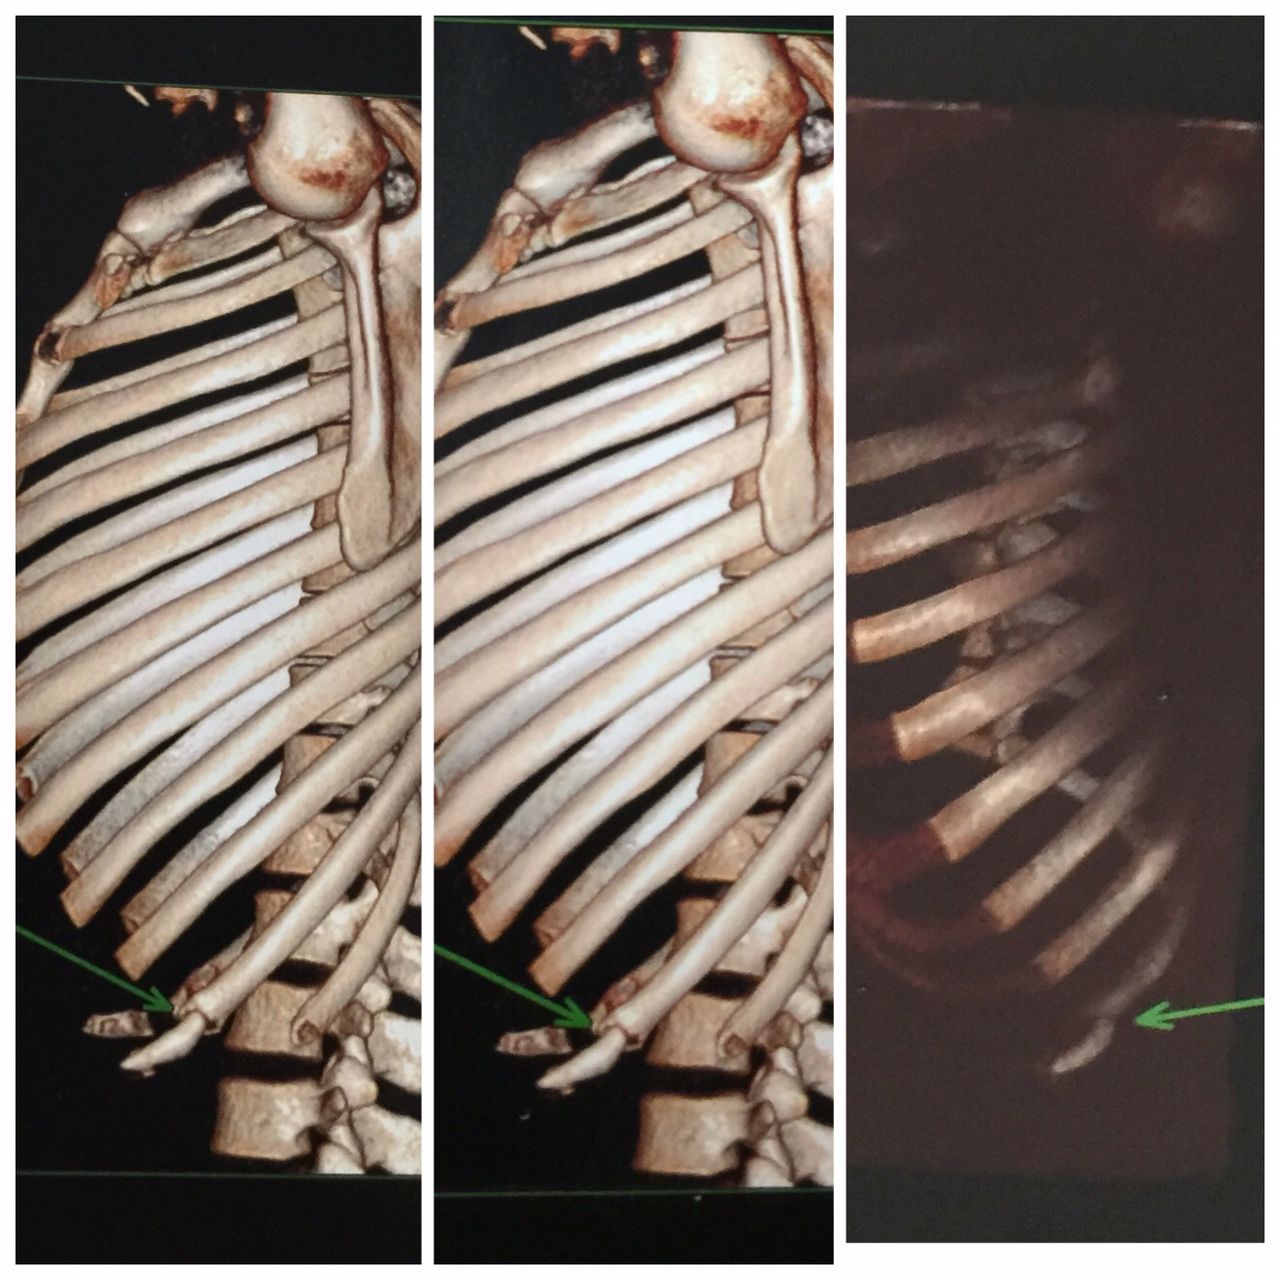

Proof? Jose Aldo’s Rib Scans Released

Jose Aldo has released a statement regarding UFC 189 and his injury. Along with his statement, Aldo provided actual pictures of his injured ribs, via scans.

Check out the photos below and see what you think:

As you can see, the green arrows are pointing to the injured rib. Do you think Aldo released these to prove to naysayers that he didn’t pull out because he was afraid.